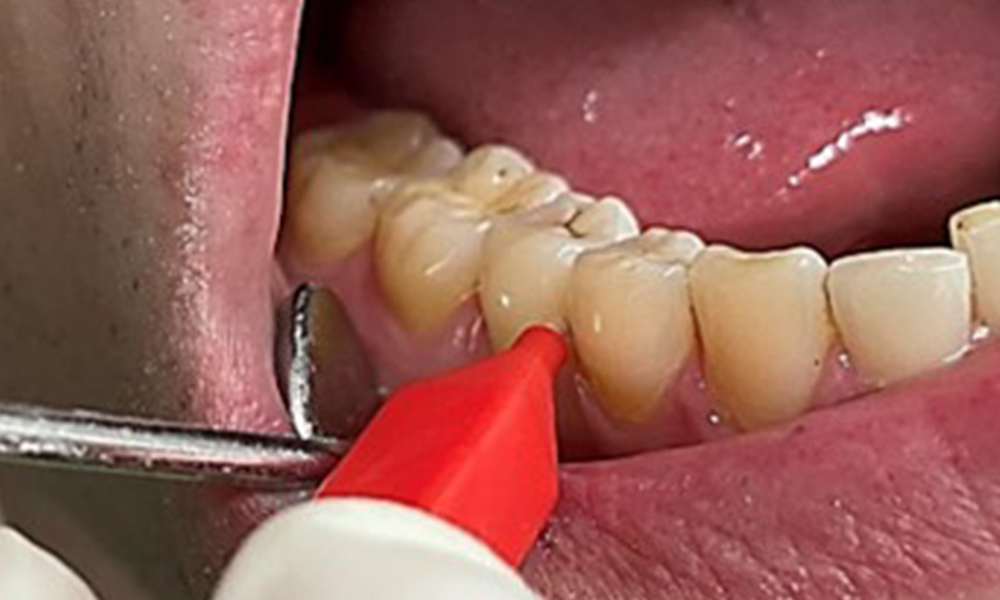

Discolorările datorate consumului de nicotină și ceai pot fi îndepărtate cu ușurință cu ajutorul unui echipament air-flow (Fig. 11).

Pentru a preveni riscul apariției emfizemului, este esențial ca, atunci când se utilizează o pudră mai abrazivă, să se intervină din direcția cervicală spre nivelul coronar, cu grijă să se evite îndreptarea vârfului de pulverizare înspre gingie. De asemenea, o bună aspirație pe partea contralaterală este absolut necesară în vederea reducerii formării de aerosoli (fig. 12).